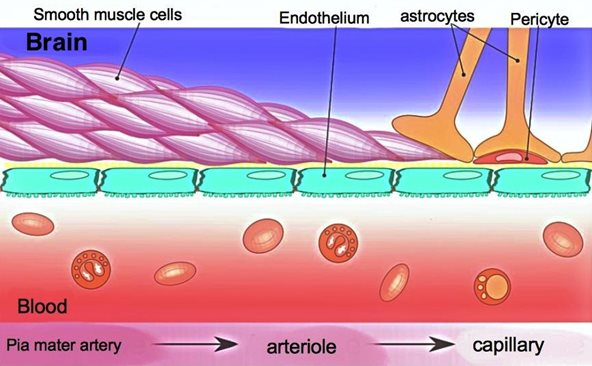

The Blood Brain Barrier

The blood-brain barrier (BBB) is a network of blood vessels and tissue that helps keep harmful substances from reaching the brain. The BBB is essential for protecting normal brain function by impeding most normal molecules from getting into the brain. No matter what, if you want to get a drug to the brain you must somehow go through the BBB. Although a nasal-to-brain pathway has been explored that can potentially bypass the BBB, several disadvantages make this solution less optimal: low bioavailability (fraction of an administered drug that reaches its target), irreversible damage of nasal mucosa, and a far more limited possible dosage. Pretty much all macromolecules (diameter ranging from about 100 to 10,000 angstroms) cannot penetrate the brain endothelium (tissues that line blood vessels). Furthermore, 98% of small molecules also can’t be transported across the BBB. Only positively charged small lipid-soluble molecules with a molecular weight < 400 Da can naturally cross the BBB. These restrictions make it challenging to design effective therapies that can enter the brain. The BBB consists of tightly packed cells and structures including endothelial cells, pericytes, astrocytes, neurons, and membranes. These components form a strong barrier in brain capillaries. The capillary endothelial cells are tightly joined without gaps, significantly limiting the passage of small molecules and proteins. Additionally, connections between these endothelial cells create a continuous barrier that restricts water-soluble substances from passing through. The permeability of the BBB is largely governed by these connections, including tight junctions, adherent junctions, and gap junctions.

More specifically, adherens junctions mainly control how substances pass through endothelial barriers. Tight junctions are crucial for maintaining the barrier that regulates the passage of materials in epithelial cells and endothelial cells, which helps keep tissues stable. Pericytes, astrocytes, and basal membrane surround the ECs and form the impermeable BBB. Additionally, efflux transporters are located in brain capillary ECs, which are further obstacles against substances entering the brain.